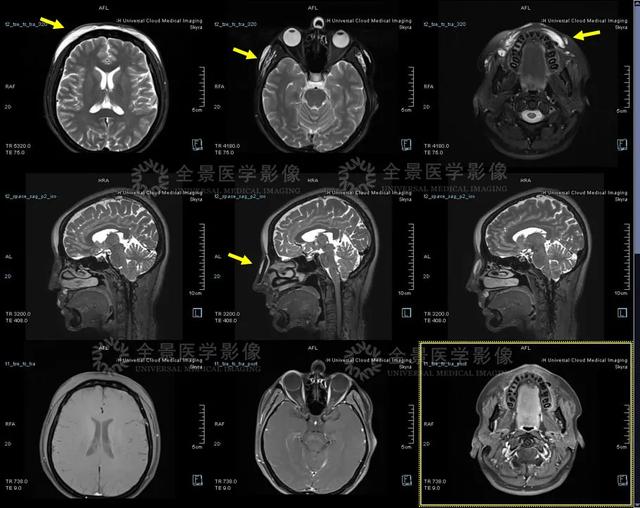

根据林女士情况,医生选择通过西门子 skyra 3.0T 磁共振的 3d 序列 T2 space,结合目前新技术——cVRT 等重建技术进行容积重建,可以再现患者的面部轮廓。

上图黄色高亮处考虑为玻尿酸注射物

从重建图中可以直观地看到患者的额部、双侧眼睑部、双侧颧部、颞部、鼻部、唇部及下颌周围皮下分布的异常信号(考虑为植入物),同时 T1 mp2rage 序列(右上)可以量化组织的 T1 值,便于直观反映各组织的 T1 值,精确判断植入物目前的状态和降解吸收情况。

3.0T 磁共振影像图

通过结合 3.0T 磁共振常规颌面部增强扫描,可以看到植入物的边界清晰,周围组织未见明显肿胀及炎性改变。